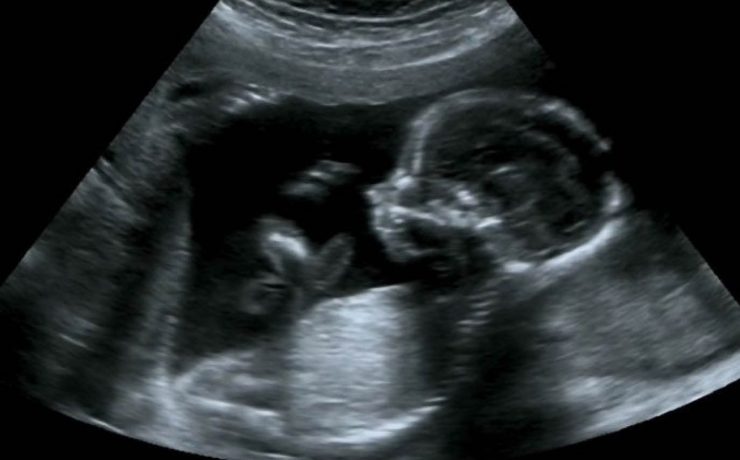

Fibroadenoma de tejido mamario ectópico axilar

Es el tumor benigno más común de la glándula mamaria de mujeres jóvenes. A pesar de que un 95% de las mujeres existe tejido mamario en la axila (cola de mama) y de que incluso en 6 de cada 100 es clínicamente evidente. Los reportes de este tumor en la